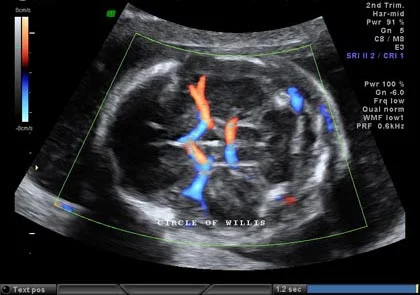

Circle of Willis

Interventricular septum

Cardiac outflow tracts